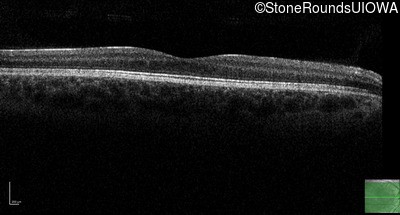

Optical Coherence Tomography - Right - 10/160 sc

Exemplar / OCT Stack

OCT Stack